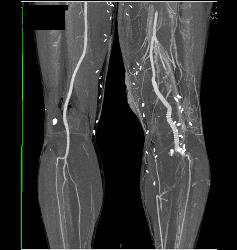

Superior Mesenteric Artery (SMA) Occlusion